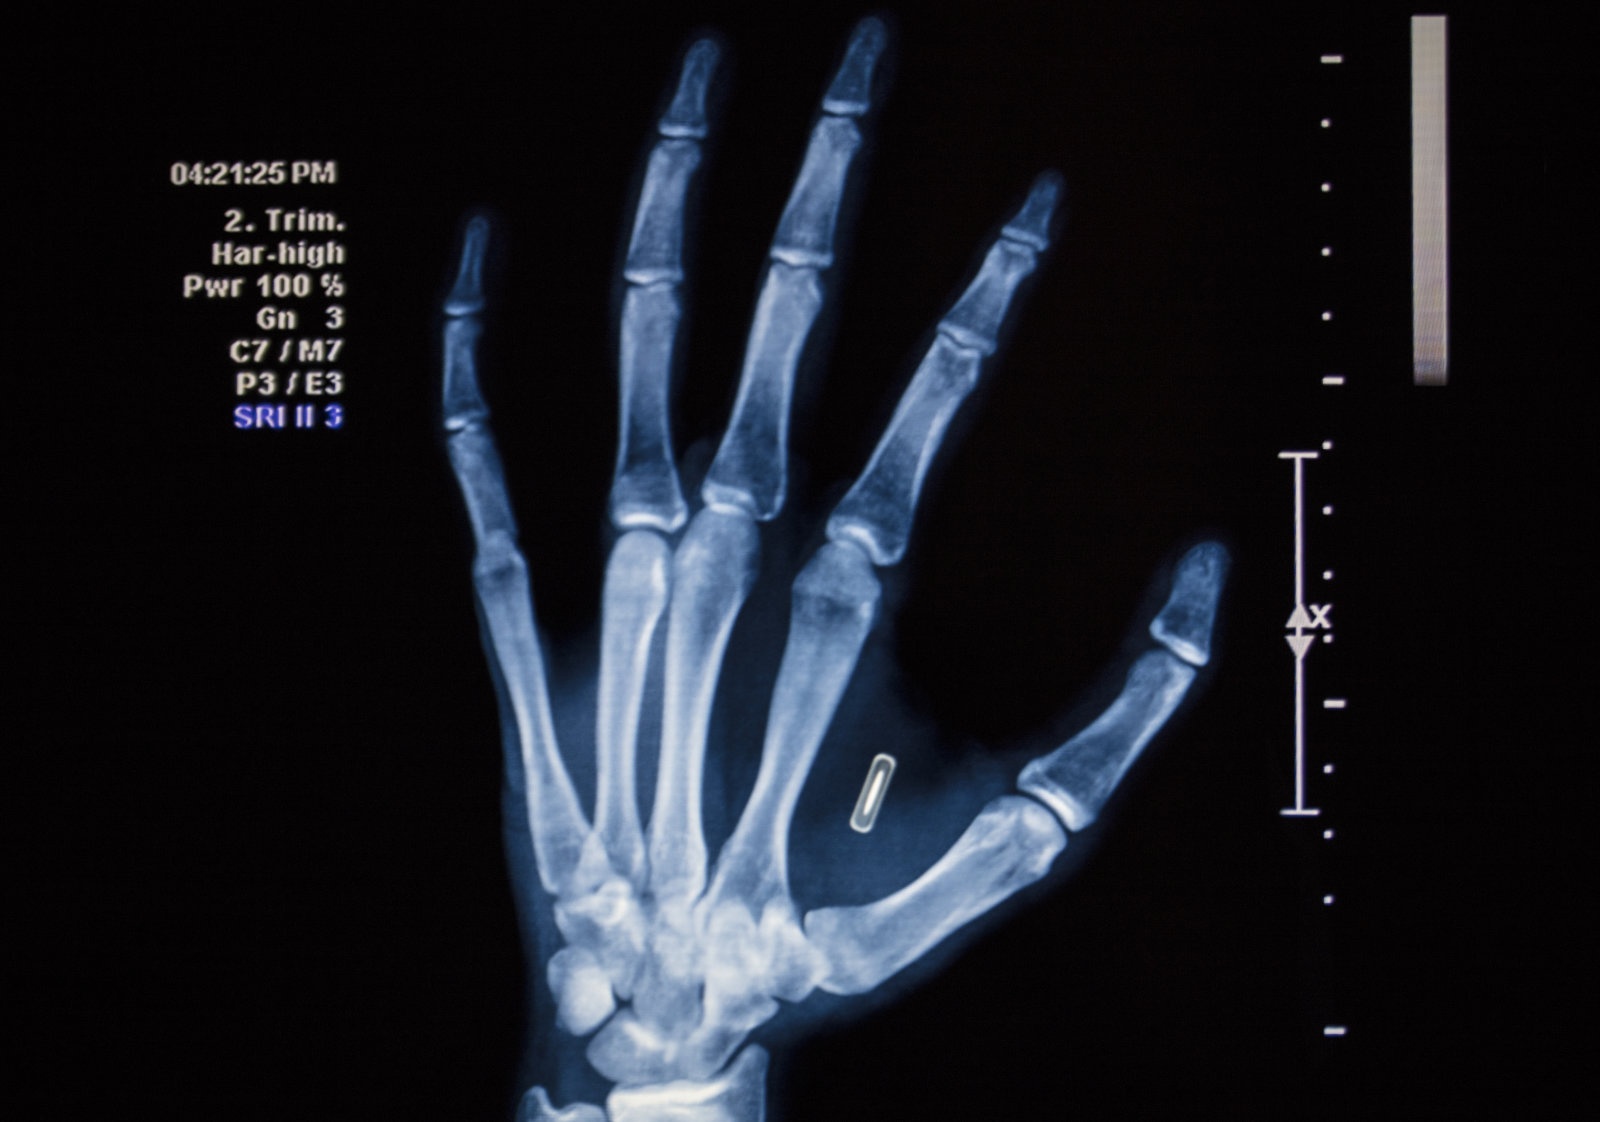

Việc cấy ghép chip cho nhân viên cũng không phải quá mới mẻ. Năm 2017, công ty Three Square Market ở Wiconsin, Mỹ đã cấy ghép chip cho hơn 80 nhân viên. Các chip RFID nhỏ bằng kích cỡ hạt gạo được cấy vào tay để nhận diện, cho phép nhân viên vận hành máy móc đúng trách nhiệm của mình. Thú vị ở chỗ, Three Square bán máy bán hàng tự động nhưng đồng thời cũng là nhà gia công cấy ghép chip.

![]() |

| Jowan Osterlund từ công ty Biohax Thụy Điển, đang cầm một con microchip cấy ghép, tương tự với loại được cấy cho các công nhân ở Vườn ươm trung tâm Stockholm. Ảnh: Engadget. |